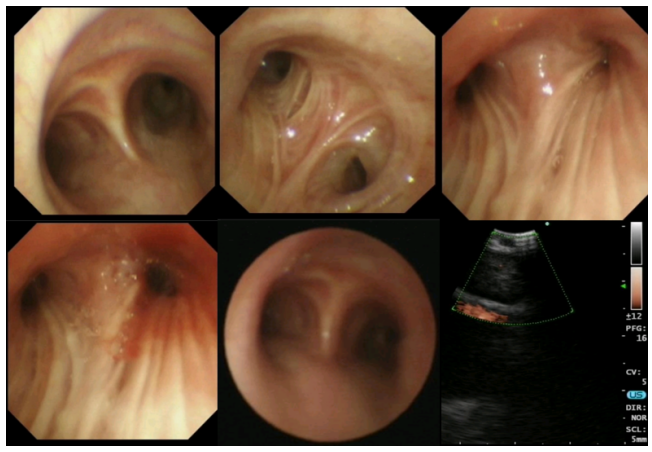

电子支气管镜及超声镜检查

显微镜下未查见细菌;抗酸染色阴性;利福平耐药检测阴性。隆突无增宽,右上叶支气管黏膜可见纵行皱襞,管腔狭窄,活检钳无法进入(图4)。取黏膜活检以及刷检和其他检查,并行超声支气管镜检查。

图片

4  气管镜下所见